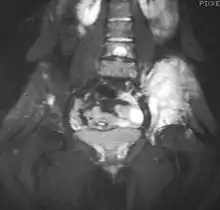

Magnetic resonance imaging slice showing Ewing sarcoma of the left hip (white area shown right)

Magnetic resonance imaging (MRI) should be routinely used in the work-up of malignant tumors. It will show the full bony and soft tissue extent and relate the tumor to other nearby anatomic structures (e.g. vessels). Gadolinium contrast is not necessary as it does not give additional information over noncontrast studies, though some current researchers argue that dynamic, contrast-enhanced MRI may help determine the amount of necrosis within the tumor, thus help in determining response to treatment prior to surgery.[27]